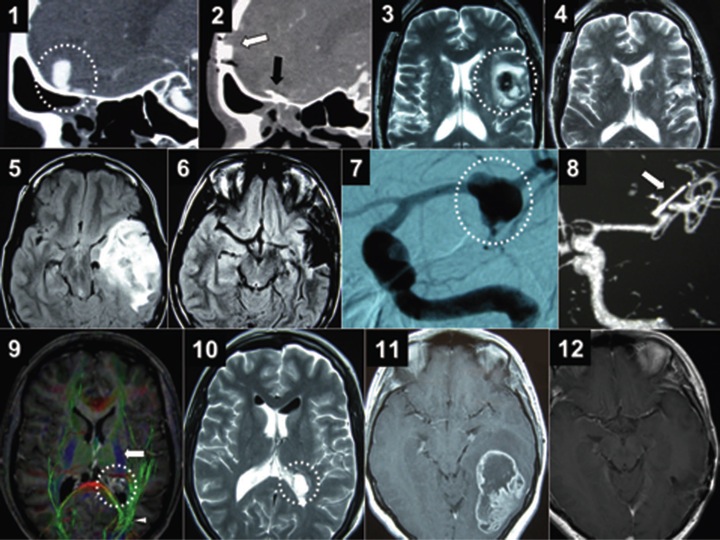

术中唤醒麻醉技术(awake craniotomy,AC)又称清醒开颅术,随着该技术的不断进步以及术中检测手段的改良,AC技术与术中电生理定位技术和神经功能检测的联合应用,在外科切除位于功能区病灶(如Broca区、Wernicke区)或中央前回运动区病灶、癫痫病灶和利用脑深部电刺激(deep brain stimulation,DBS)治疗帕金森病或强迫症中越来越受到重视。

清醒开颅术使用术中功能性MR成像来描绘病变与大脑的言语和运动通路之间的关系。与在全身麻醉下进行手术的患者相比,清醒开颅手术的患者术后早期运动结果更好,晚期轻微并发症更少,住院时间更短。

在清醒开颅术期间,患者处于镇静状态,而正在运行的神经外科医生从大脑表面的传感器或电较网格中诱发电刺激。然后唤醒患者,并使用他或她对大脑皮层和深部区域刺激的有意识反应来实时调整大脑的运动和言语图。该图允许外科医生在手术过程中较大水平地去除肿瘤,同时尽可能地保留患者原有的神经功能组织,尽量不对功能区造成伤害。

2、协助确定病灶切除范围(extent of resection,EOR):在现代神经外科手术中,为确定EOR,已经建立了多种辅助措施,例如肿瘤5。氨基乙酰丙酸荧光染色法、术中MRI、术中超声和导航系统等,但如果病灶位置比邻功能区,与全身麻醉(general anesthesia。GA)下手术相比,AC技术明显有利于病灶的扩大切除H1。AC技术旨在更大水平保留重要神经功能的基础上,更大水平地切除病灶。而临床数据也支持此观点,认为AC技术与EOR更大、同时术后神经功能损伤发生率更低有关。